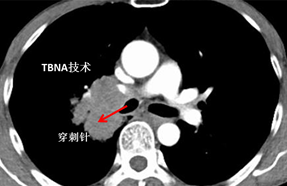

病例一:

(胸部增强CT提示肿块在右主支气管管腔外)

(通过CT片测得病灶于标记点的距离,确定进针角度及深度)